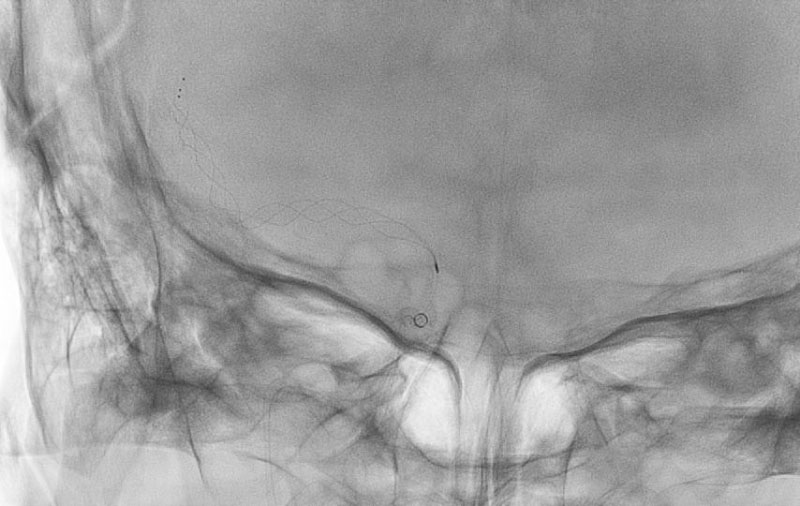

'22年7月

前交通動脈瘤

60代

大阪府の病院

No.1251 手術中